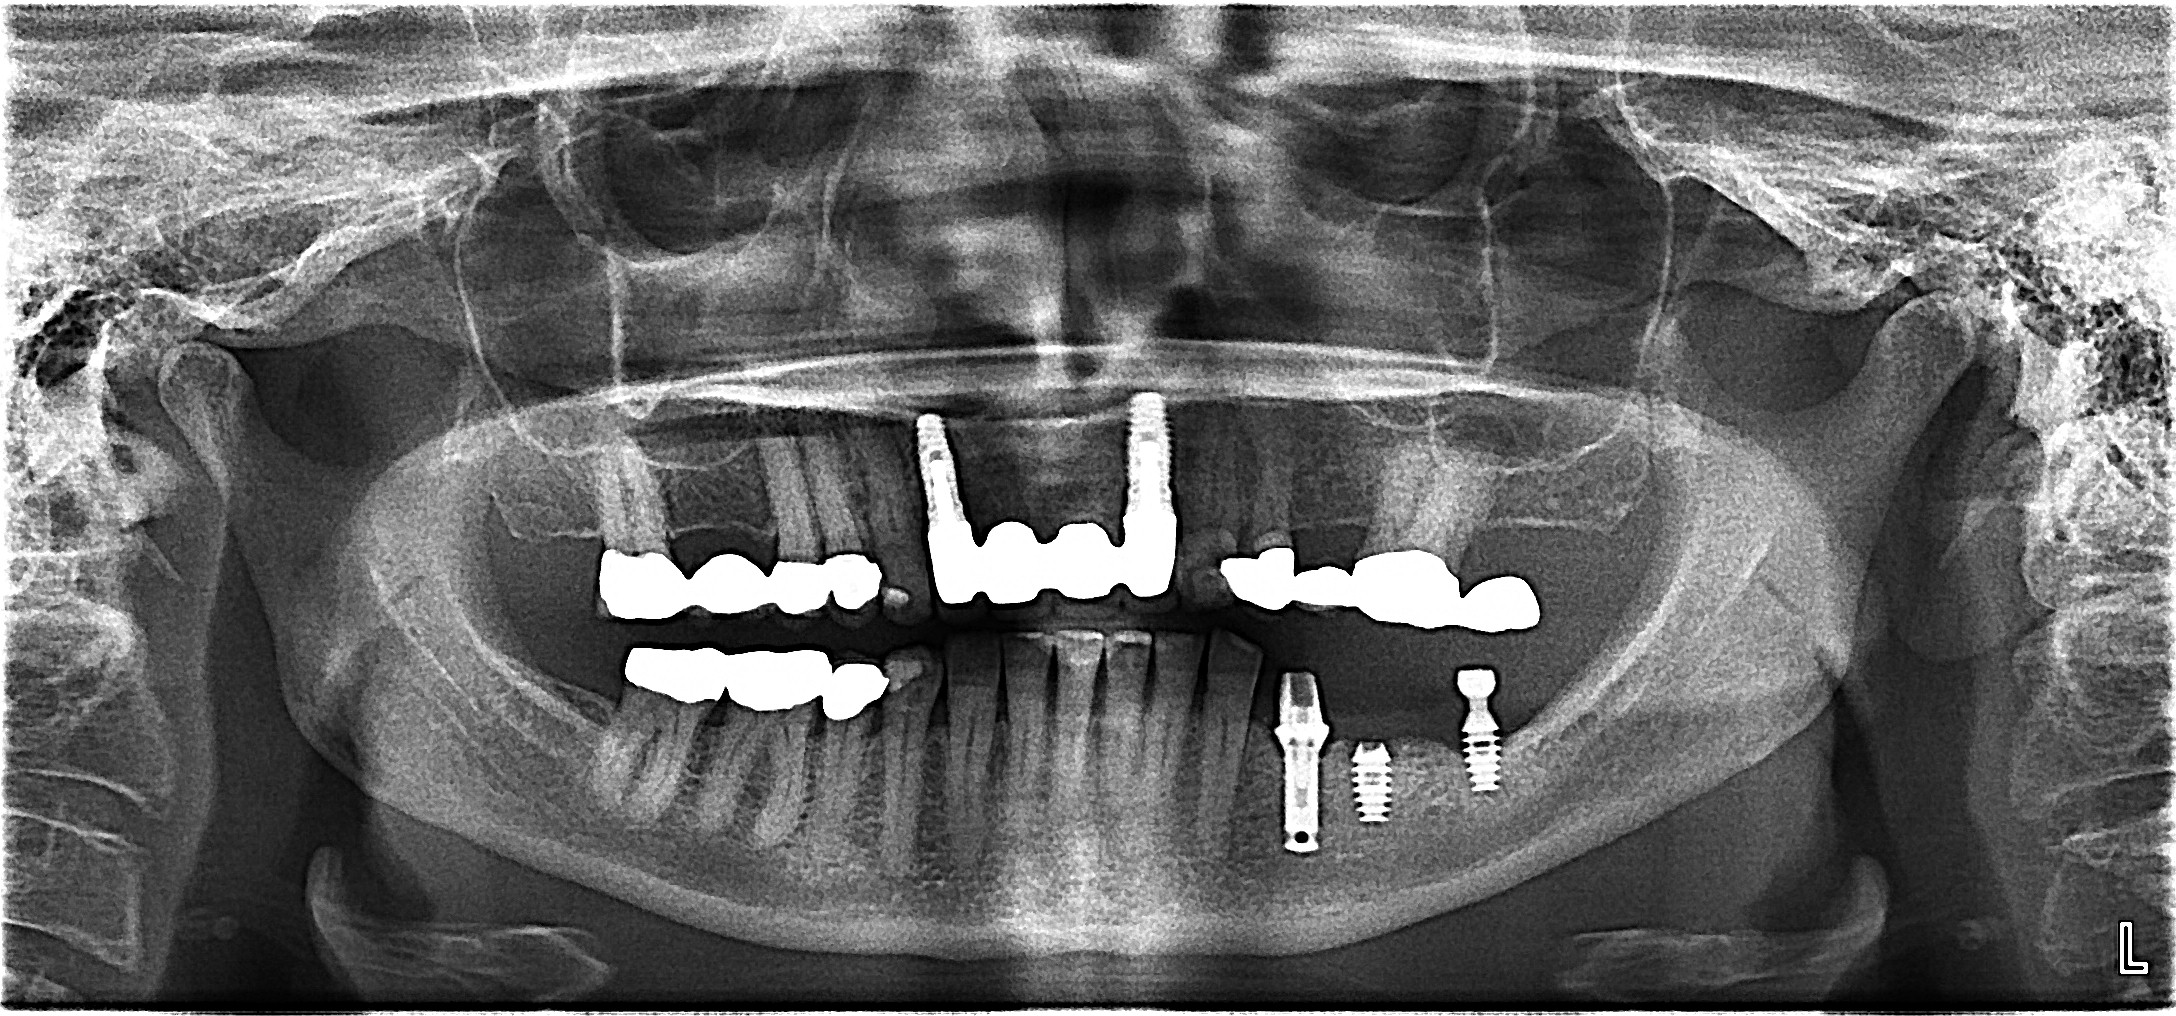

A panoramic radiograph is a panoramic scanning dental X-ray of the upper and lower jaw. It shows a two-dimensional view of a half-circle from ear to ear.

The X-rays use small amounts of radiation. Panoramic X-rays show a broad view of the jaws, teeth, sinuses, nasal area, and temporomandibular (jaw) joints. These X-rays show problems such as impacted teeth, bone abnormalities, cysts, solid growths (tumors), infections, and fractures